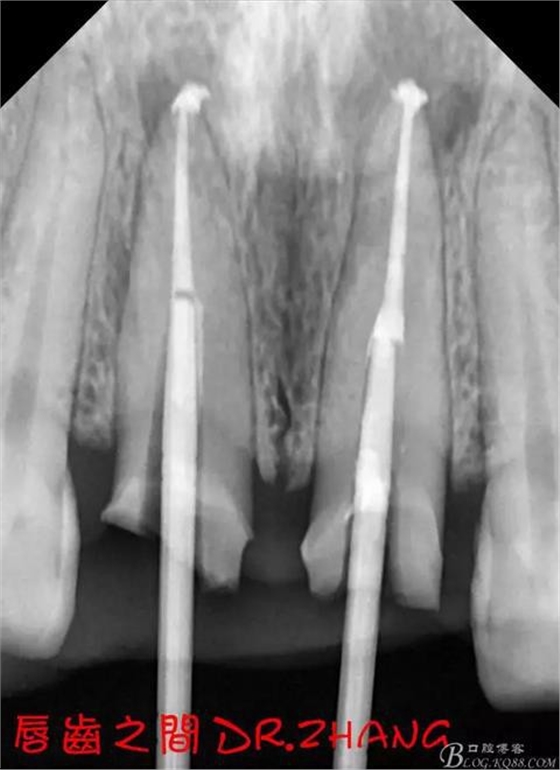

復(fù)診:腫脹明顯消失 患者自訴感覺(jué)良好 溝通后決定拆除11 21兩顆烤瓷冠后重新修復(fù) 去冠器直接去冠 去除11根管內(nèi)的充填物 15#K銼疏通根管 11 21根長(zhǎng)均為16MM平斷面 薩尼S3系統(tǒng)機(jī)擴(kuò)至2S 期間不斷用氯己定和鹽水交替沖洗 吸潮紙尖干燥根管后06 25#試尖

思博安熱牙膠系統(tǒng)根充 燙斷至根尖三分之一處后纖維樁恢復(fù)牙體組織